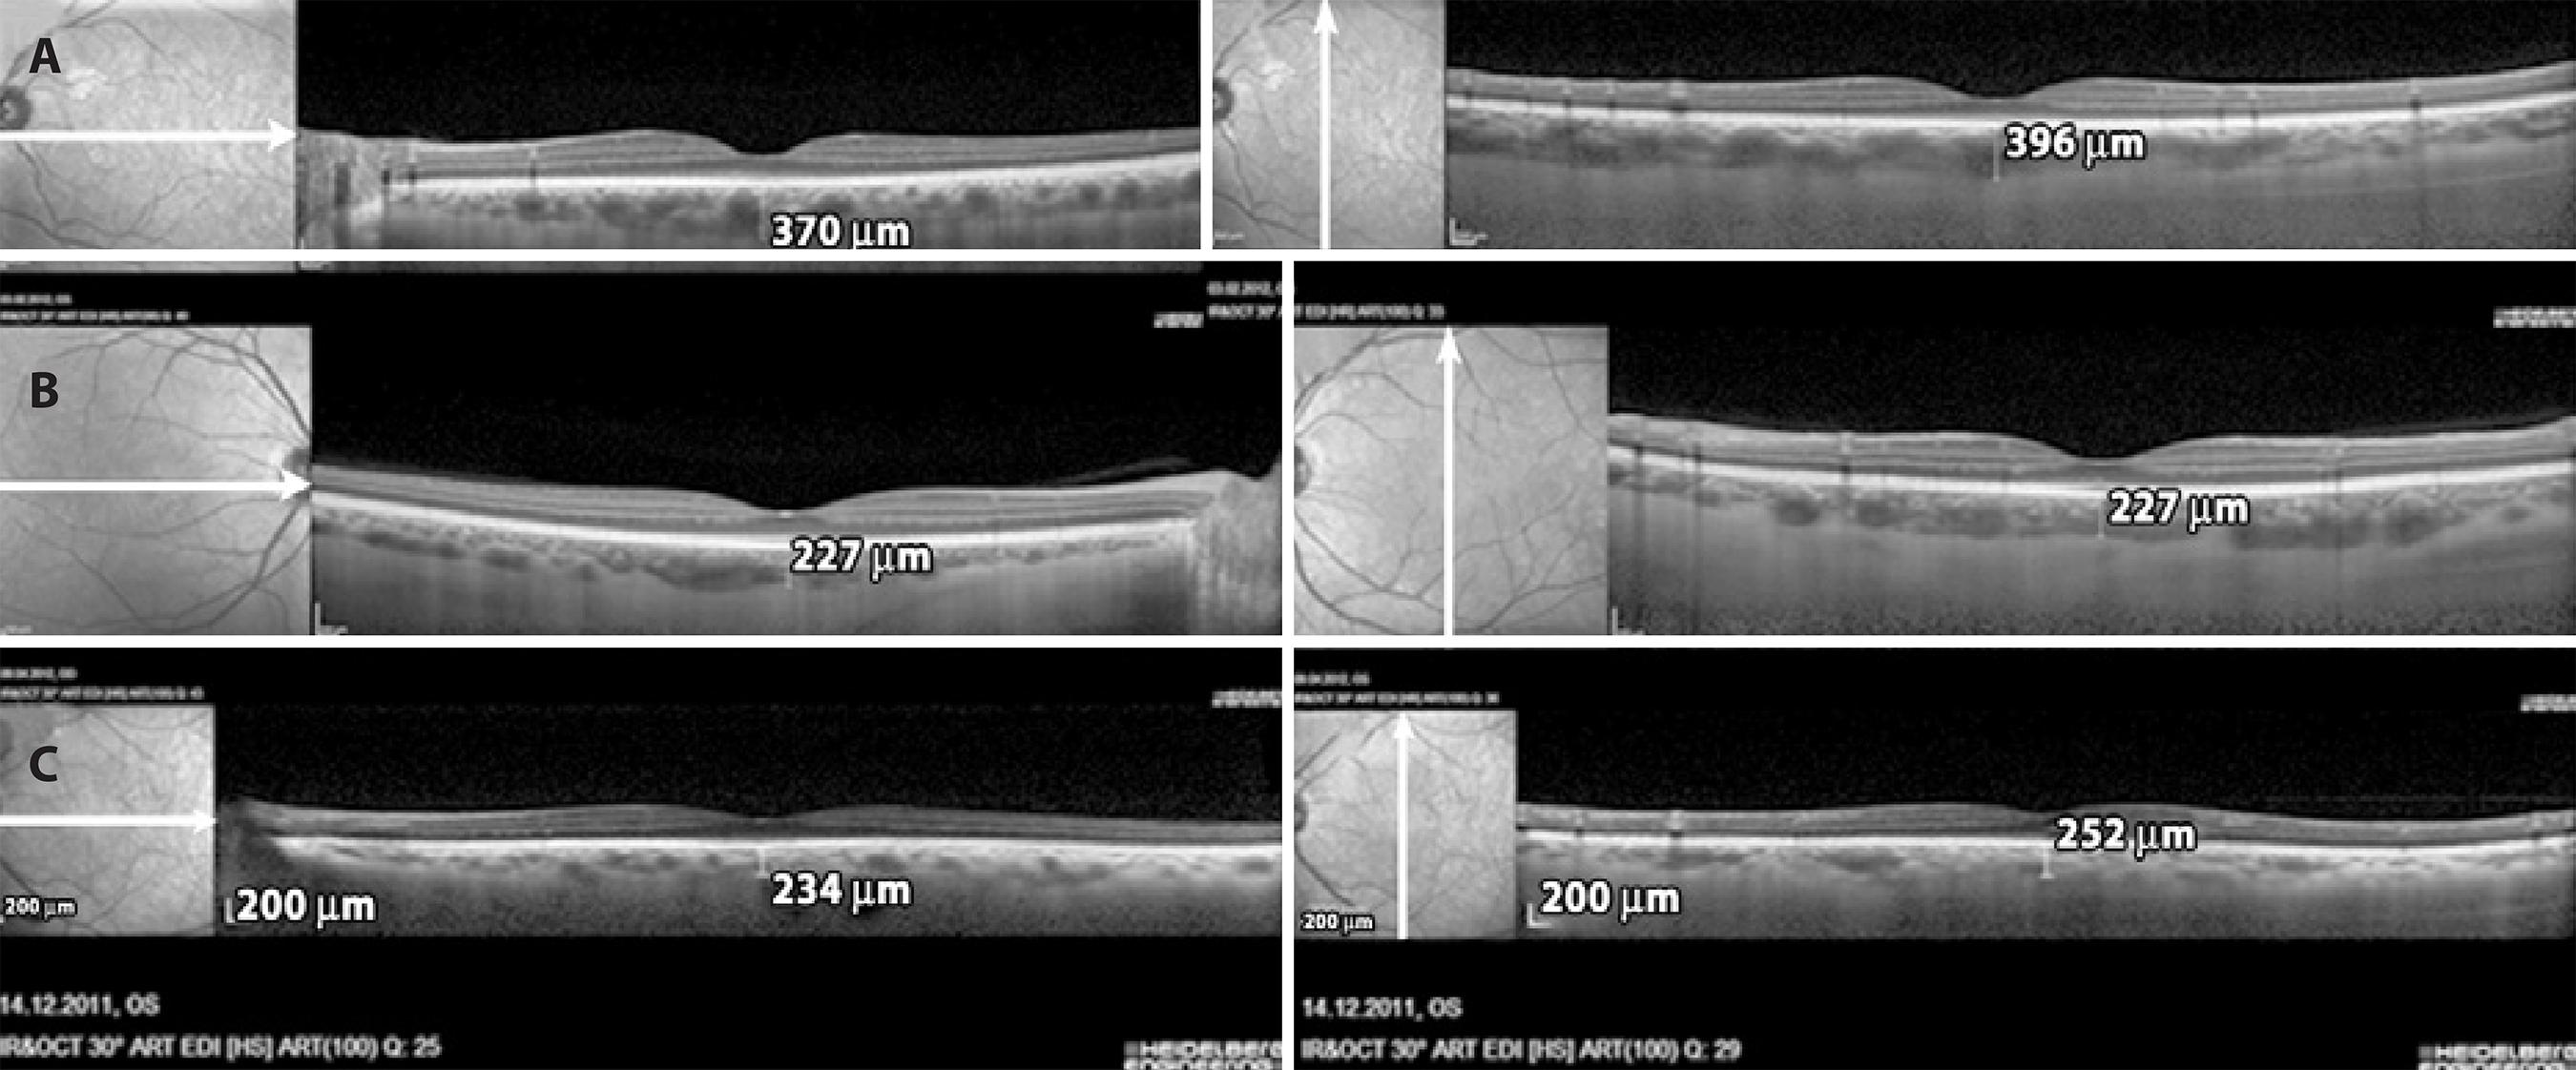

OCT images were obtained in the EDI mode of a spectral domain OCT (Spectralis, Heidelberg Engineering, Heidelberg, Germany). For EDI-OCT, foveal-centered vertical and horizontal two line scans were performed in an assay of 100 frames, 30°, and high resolution (HR). SFCT was calculated by obtaining mean measurements of the vertical and horizontal scans thicknesses. The choroidal thickness was manually measured via the software in the OCT device with magnified images (× 200). The distance from the hyperreflective line at the base of the retina pigment epithelium layer to the hyporeflective line in the outer sclerochoroidal interface was accepted as the choroidal thickness (Figure 1). When necessary, contrast assays were altered to obtain improved images of the choroidal layer. Pupils were not dilated for the test. Recordings with a quality (Q) below 20 were excluded. Choroidal thickness evaluations were performed by a single examiner (MO) who was blinded to patient diagnoses. The left eye of each patient was tested if not accompanied by exclusion criteria.

Figure 1 Measurements of subfoveal choroidal thickness using the EDI mode of spectral domain OCT (Spectralis, Heidelberg Engineering, Heidelberg, Germany). A) A mild OSAHS patient; B) A moderate OSAHS patient; C) A severe OSAHS patient.